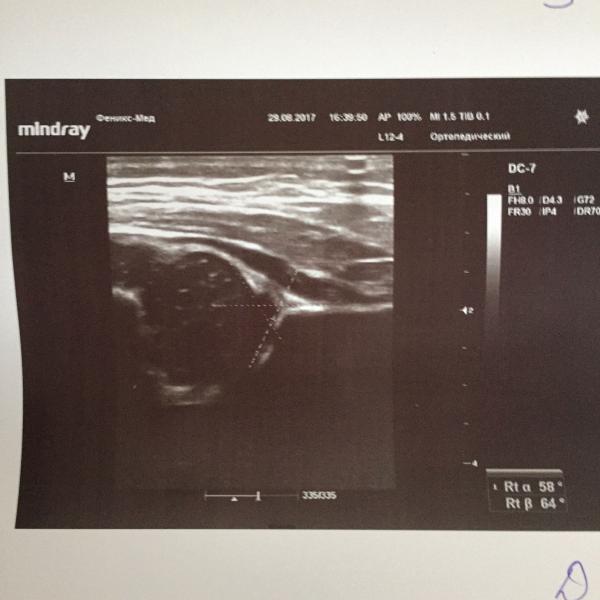

расскажите, как развивались ваши дети, у которых было как у нас- незрелые, сглаженные тазобедренные суставы. знаю, что это у тех, кто в пузе долго на попе сидел. врачи говорят- надо наблюдать. и широкое пеленание. пеленание- это не про нас, точно... больше ни слова никто не говорит. скоро к ортопеду, может он что-то более подробно расскажет...

В 3 месяца УЗИ контроль, суставы зрелые. А ортопед вообще сказал ничего делать не надо.